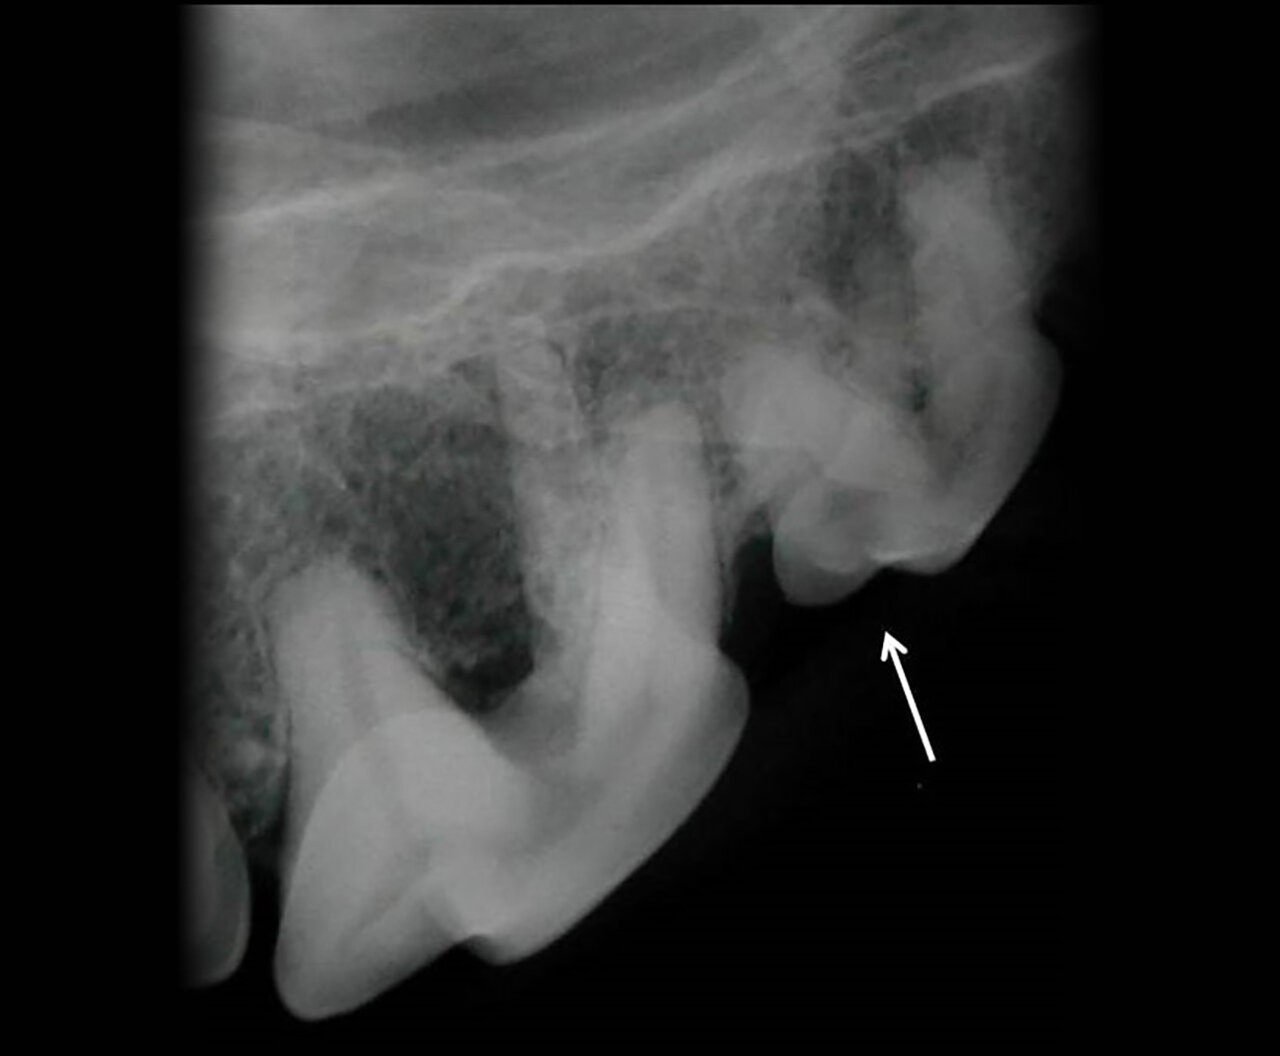

- La superposición del orificio mentoniano sobre la porción apical de la raíz en el canino mandibular de un perro produce una apariencia similar a la zona radiolúcida que aparece cuando existe patología periapical.

- En el gato, el foramen mentoniano se encuentra en el espacio interdental entre el diente canino y el tercer premolar mandibular o a nivel de este último (imagen 5).